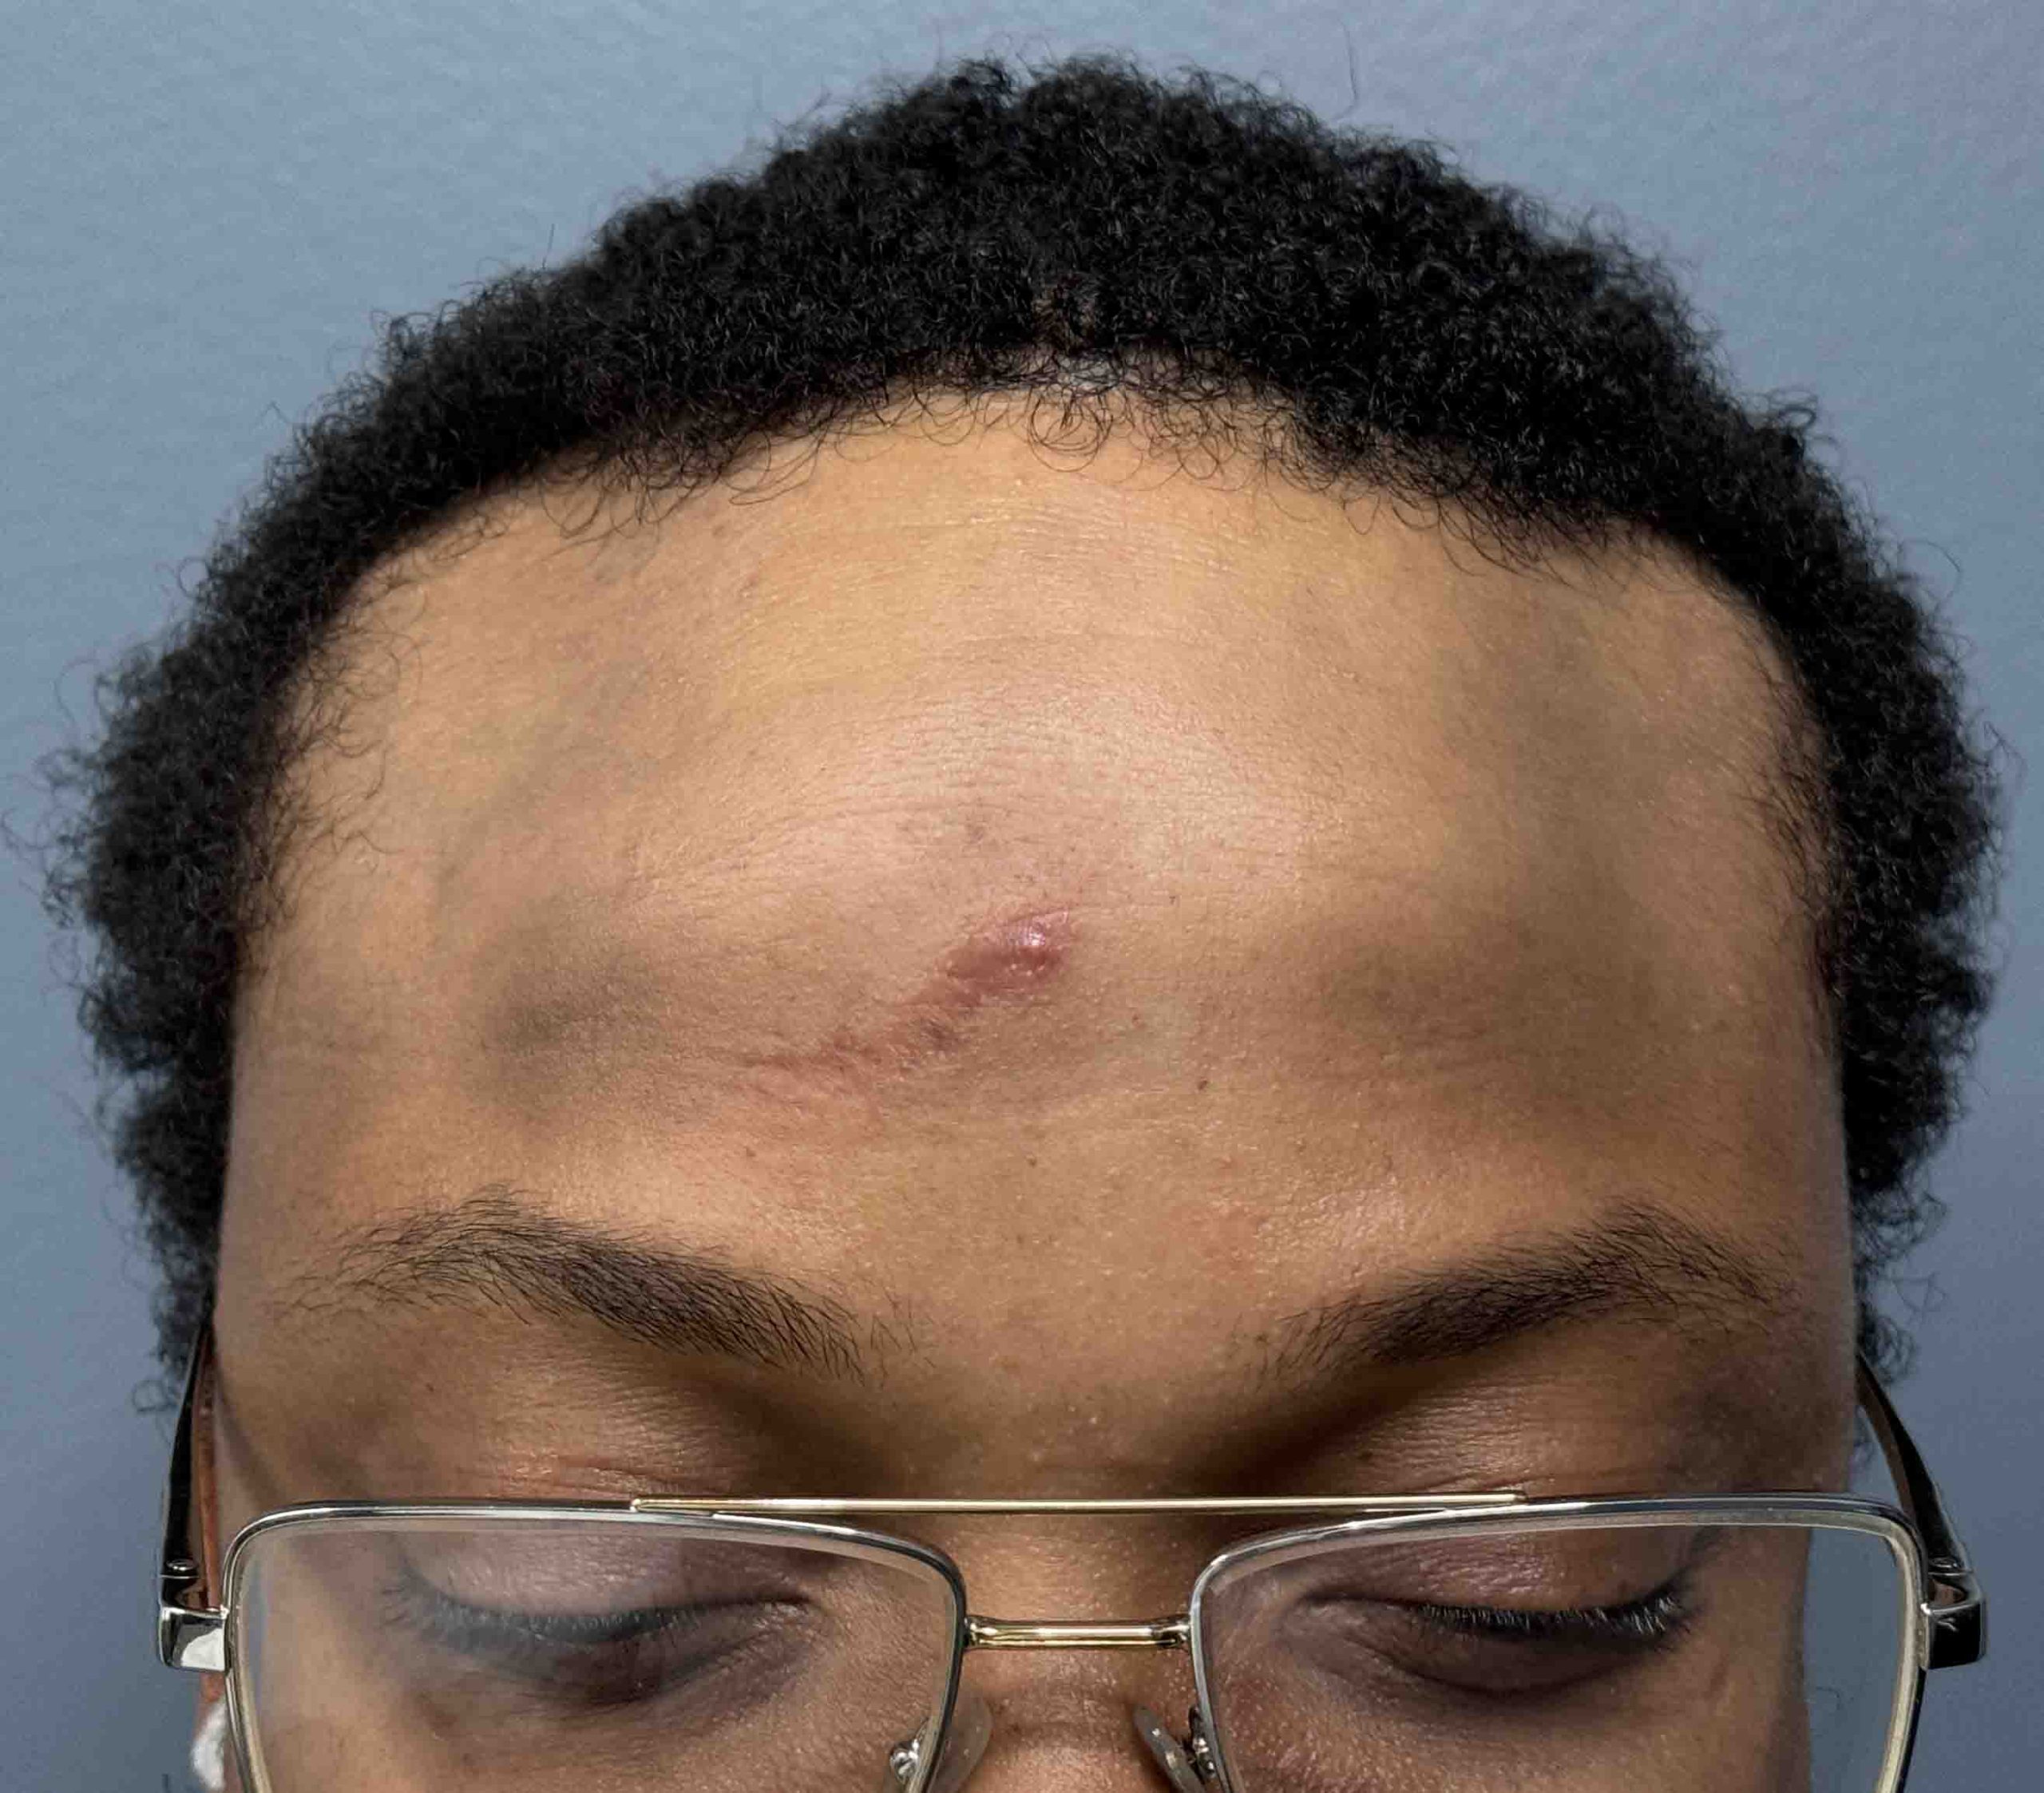

Patient 27

Desire for reduction of skull ridge reduction.

Anterior sagittal skull ridge reduction by bone burring.

Desire for reduction of skull ridge reduction.

Anterior sagittal skull ridge reduction by bone burring.